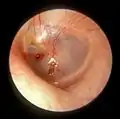

The oval perforation in this left tympanic membrane was the result of a slap on the ear

A subtotal perforation of the right tympanic membrane resulting from a previous severe otitis media